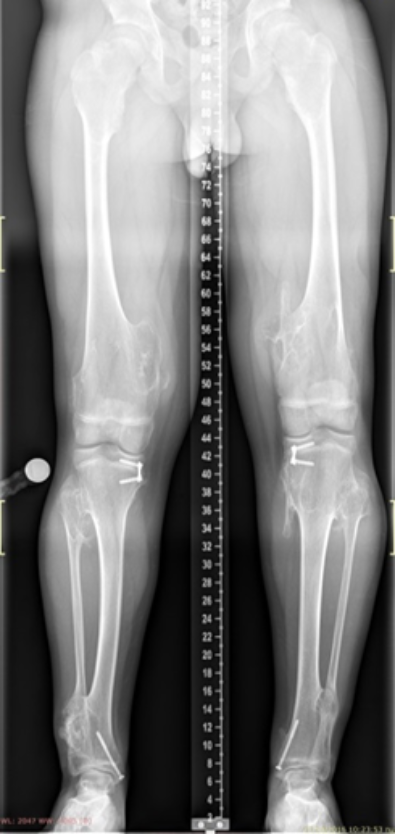

The images show a case of multiple osteochondroma which was operated by

Dr. Zenios in order to restore the mechanical axis.

Post-operative